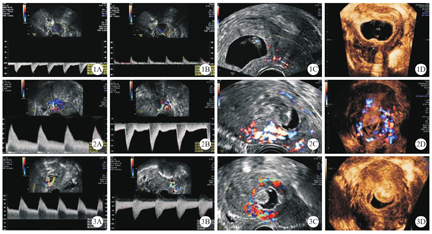

结合病史、临床症状及经阴道和(或)腹部彩色多普勒超声检查结果,对CSP进行综合诊断。CSP临床诊断标准为:既往有剖宫产术分娩史,本次妊娠有停经史,有或无腹痛及阴道流血,血清β-人绒毛膜促性腺激素(human chorionic gonadotropin,hCG)水平升高[6,7]。CSP超声诊断标准为:宫腔和宫颈管内未见孕囊;孕囊或妊娠组织位于子宫前壁峡部;孕囊种植于子宫肌层,膀胱与孕囊间子宫肌层组织缺如或消失[8,9]。若经阴道彩色多普勒超声检查无法确诊CSP,则再进行三维超声检查,予以明确诊断[10]。根据孕囊与子宫肌层的关系,超声下可将CSP分为:浅表型、部分型和完全型CSP 3种类型(图1,图2,图3)[11]。

本研究纳入标准:根据CPS临床、超声诊断标准[6,7,8,9],于本院首次诊断为CSP,并且术中经活组织病理学检查确诊为CSP者;临床病例资料完整者。排除标准:于外院诊断为CSP后,转诊至本院接受治疗者。

本研究采用GE Voluson E8彩色多普勒超声诊断系统(美国GE公司),对所有受试者进行经阴道超声检查。